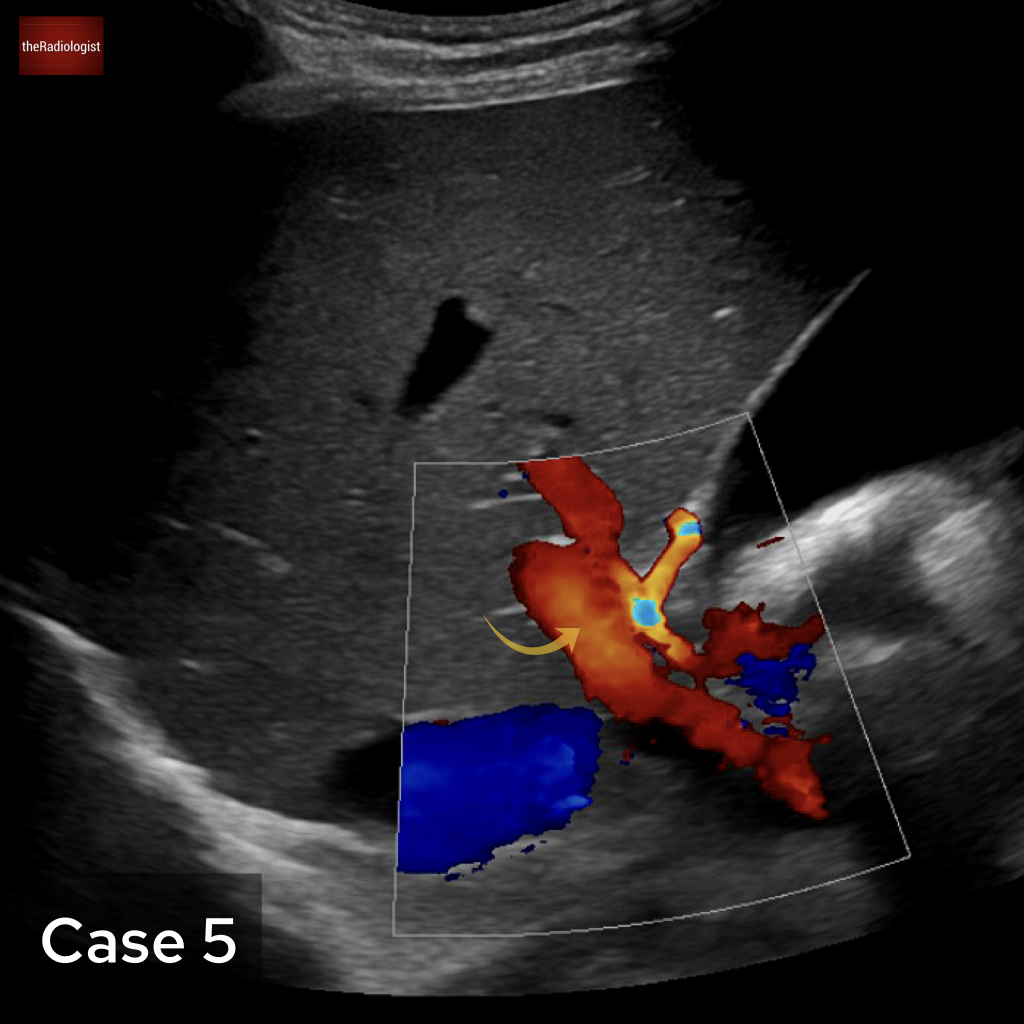

Case 5

An abdominal ultrasound for this case. What is the arrow pointing at?

Choose one from the following: